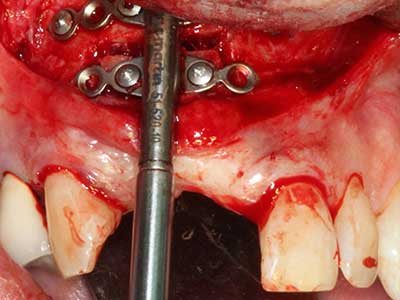

Bei der Knochenblockentnahme zeigen sich weitere Vorteile für die Piezochirurgie: Neben der bereits beschriebenen hohen Präzision bei der Osteotomie stellt sich gerade die Verwendung der dünnen Sägespitzen als besonders materialschonend heraus. Bei der Verwendung insbesondere von Lindemannfräsen sind mit deutlich höheren Entnahmeverlusten durch die dickere Instrumentenspitze zu rechnen (Lakshmiganthan, Gokulanathan et al. 2012). Die insbesondere bei retromolar entnommenen Blocktransplantaten notwendige basale Abtrennung wird durch speziell hierfür vorgesehene rechtwinklige Sägen erleichtert, so dass die Piezochirurgie als präzises, übersichtliches und sicheres Verfahren zur retromolaren Knochenblockgewinnung angesehen wird (Happe 2007) (Abb. 1-12).

Knochengewebe ist nicht nur rein mineralisch, sondern auch in wesentlichen Anteilen aus Kollagenfasern aufgebaut. Dies gewährleistet neben einer guten Druckfestigkeit eine gewisse Flexibilität, welche für die Durchführung von Augmentationen genutzt werden kann. Bei der klassischen Expansionsplastik im Sinne eines Bone Splittings wird der atrophierte Kieferkamm in seiner Längsachse gespalten und nach Erreichen einer ausreichenden Osteotomietiefe vorsichtig aufgedehnt (Abb. 13-16), idealerweise ohne den Kiefer wesentlich zu deperiostieren (Brugnami, Caiazzo et al. 2014, Stricker, Fleiner et al. 2014). Bewährt haben sich Schrauben- und Plattensysteme mit zunehmender Expansionsdistanz, um die beiden Knochenlamellen unterhalb der Bruchschwelle voneinander zu distanzieren. In der Regel werden Restknochenbreiten von mindestens 3-4 mm gefordert (Chiapasco, Zaniboni et al. 2006), um eine ausreichende Flexibilität und knöcherne Bedeckung der einzubringenden Implantate zu gewährleisten. Ggf. kann eine ein- oder beidseitige vertikale Entlastungsosteotomie die Flexibilität verbessern. Als Alternative zur klassischen Technik wurde eine Kombination mit weiteren augmentativen Techniken vor allem auf der bukkalen Seite beschrieben.